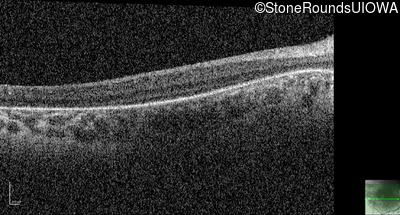

Optical Coherence Tomography - Right - No Light Perception

Exemplar / OCT Stack